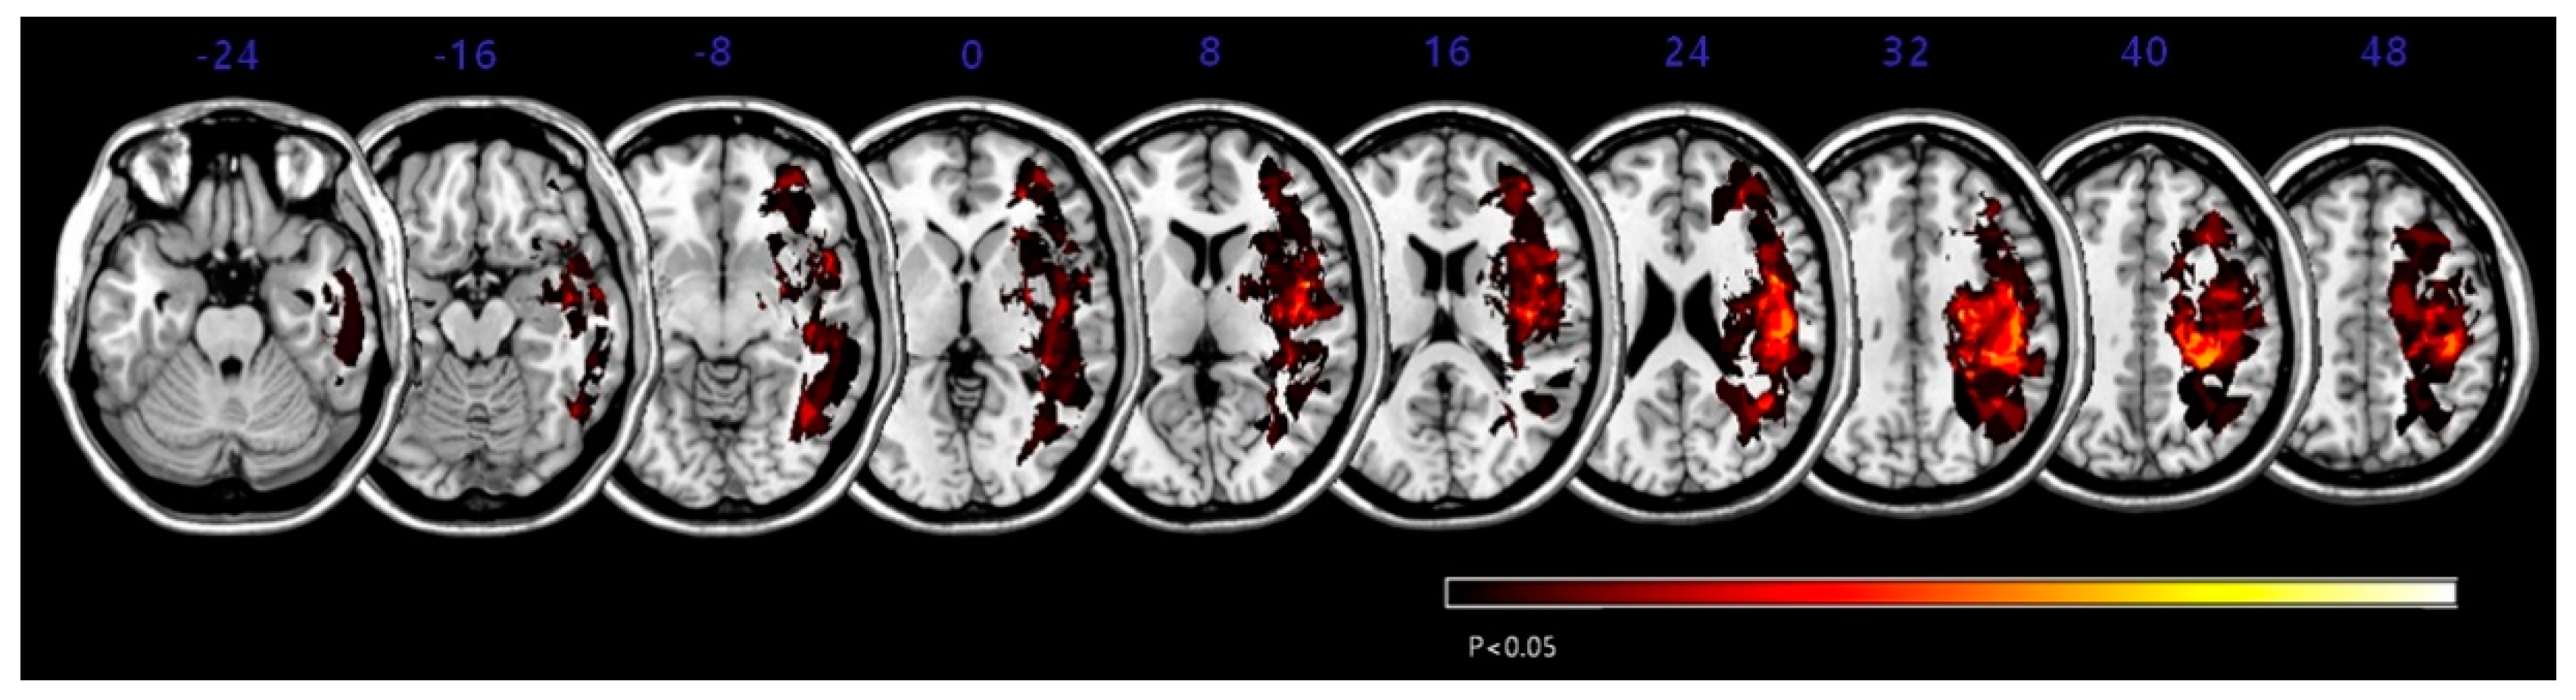

The overlapping lesions in the brains of all stroke patients were created on a standard MNI space brain. (Figure 1; the color represents the frequency of overlap). The VLSM method with SnPM (statistical non-parametric mapping) demonstrated the region that corresponded to SCP (Figure 2 and Table 3). Before adjusting the lesion volume, the precentral gyrus, postcentral gyrus, inferior frontal gyrus, insula and subgyral parietal lobe of the right hemisphere were noted for producing the lateropulsion. However, after adjusting the lesion volume as nuisance covariates, no statistically defined lesion areas were associated with SCP scores in Table 3.

Figure 1. Lesion overlap map for all subjects (n = 50). The map of overlapping lesion areas in the brains of all stroke patients was created in standard Montreal Neurologic Institute (MNI) space. Colors denote the frequency of overlap.